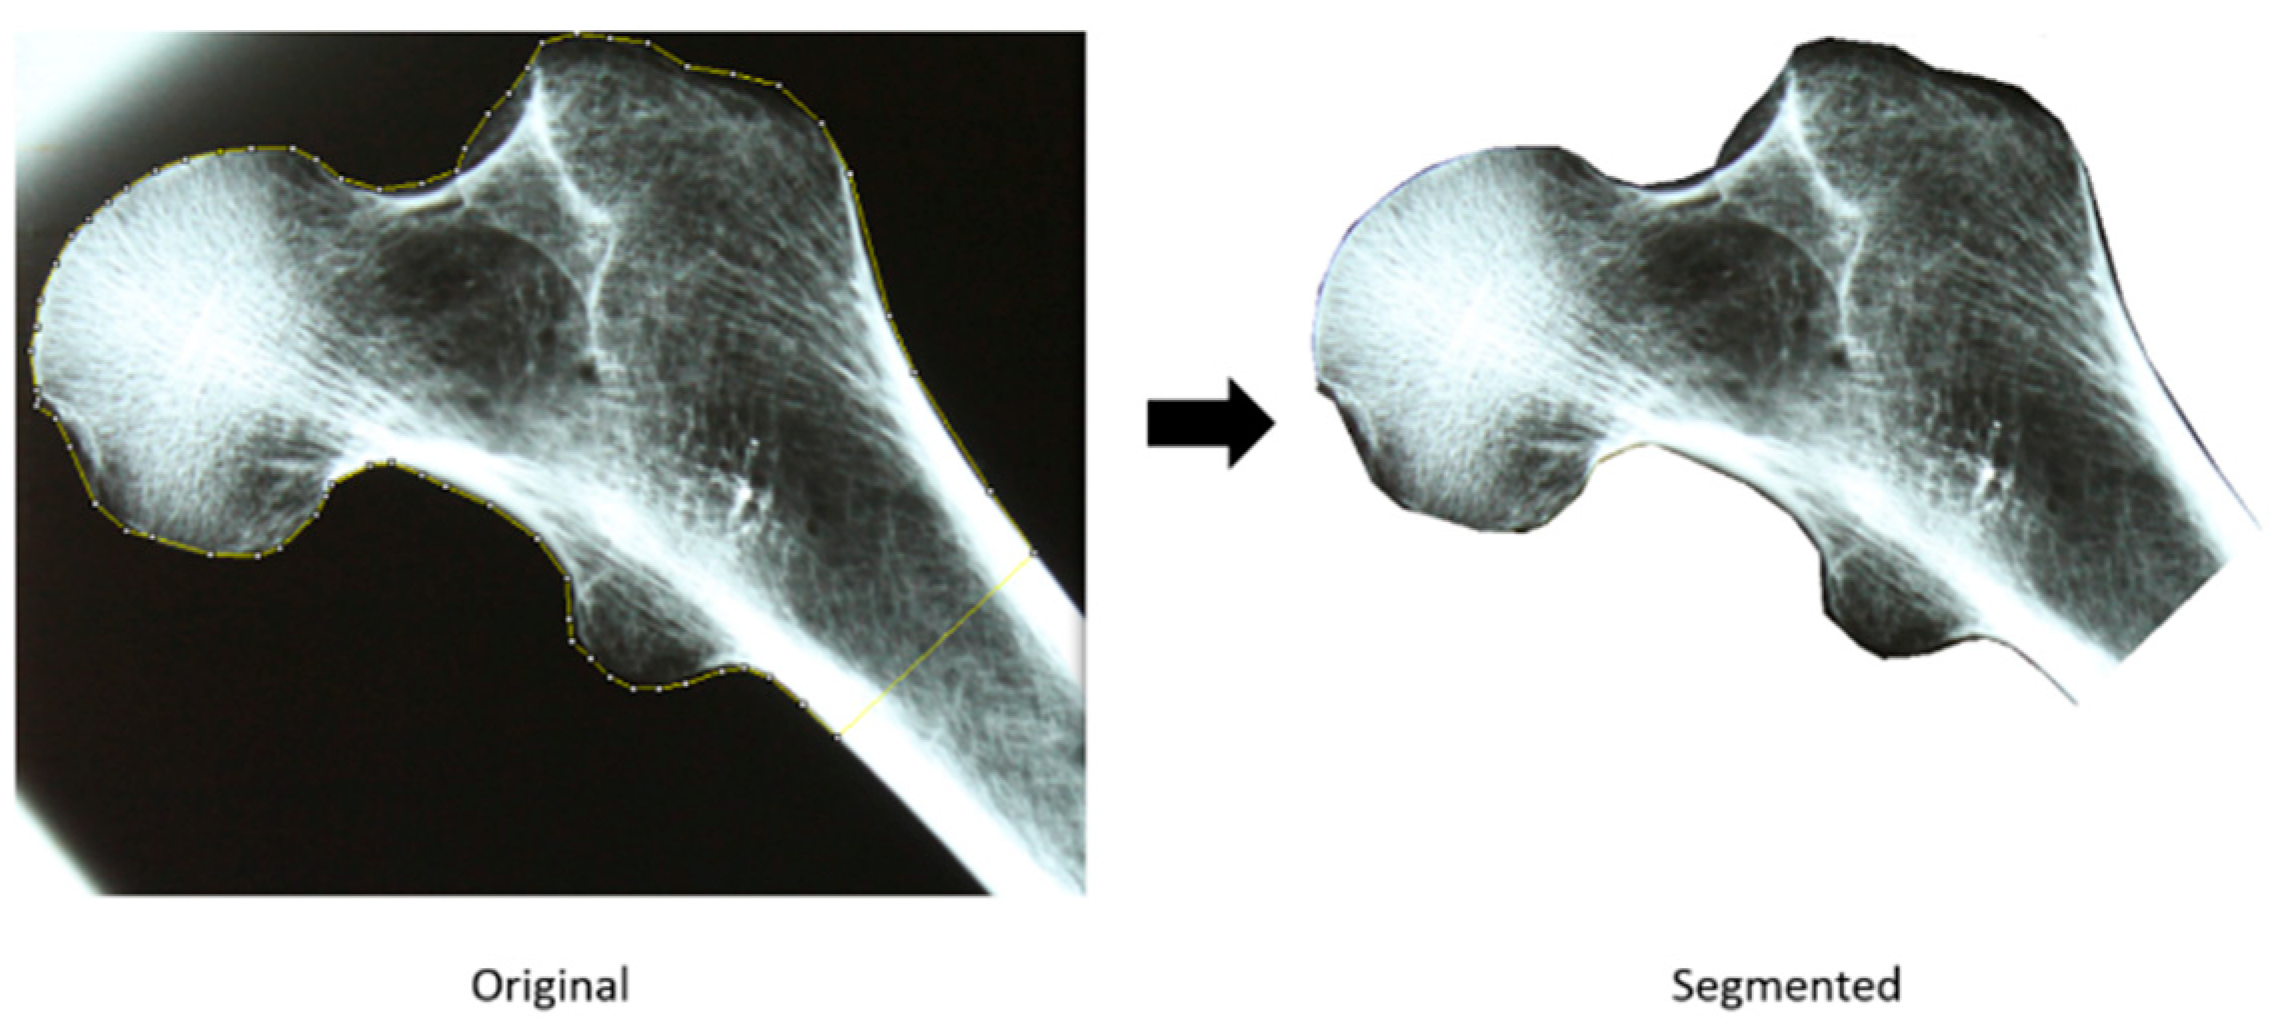

2.2.1. Acquisition and Segmentation